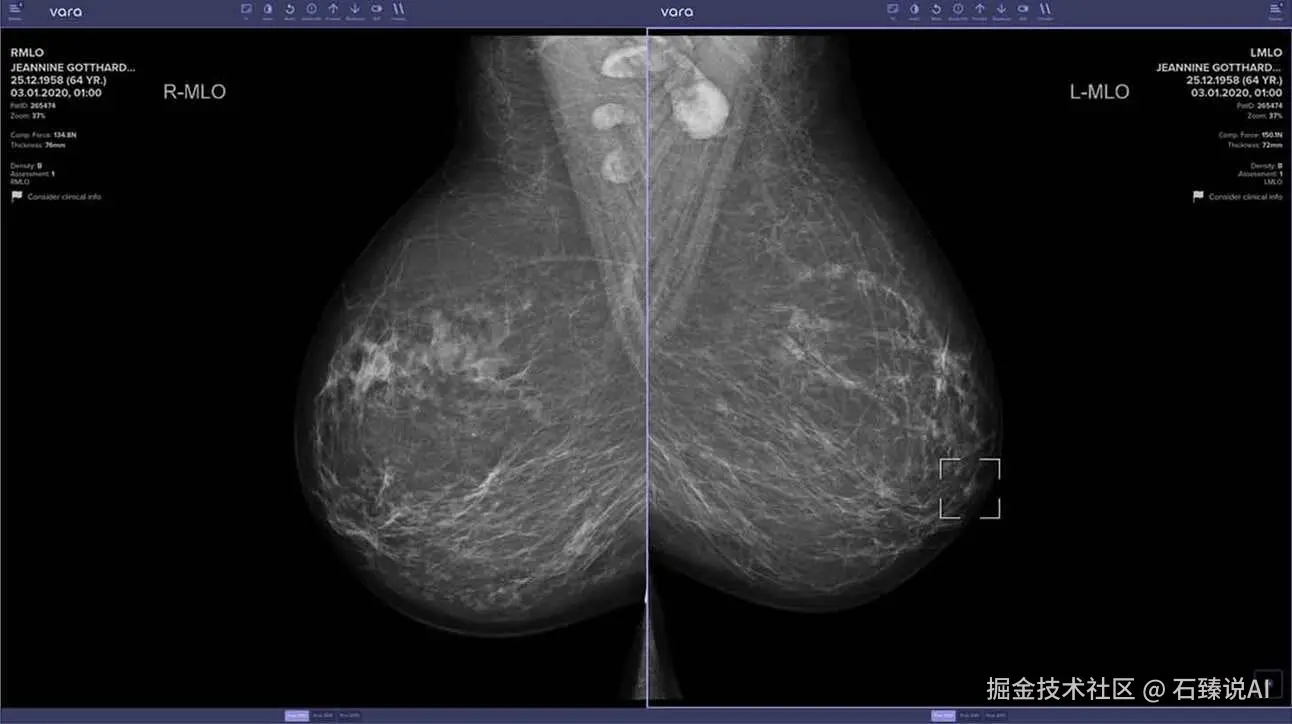

🔬 AI 在癌症检测中的突破性研究

概述: 德国吕贝克大学的研究人员刚刚发表了一项新研究,展示了迄今为止最大规模的 AI 在乳腺癌筛查中的实际应用,发现 AI 可以将癌症检测率提高 17% 以上。

详情:

• 该研究涉及 119 名放射科医生,他们可以自愿选择是否使用 AI,超过 46 万名女性接受了筛查。

• 使用 AI 支持的放射科医生的癌症检出率为每 1000 次筛查 6.7 例,比传统方法提高了 17.6%。

• 对于建议的活检,65% 的 AI 辅助阅读确认了癌症,而没有 AI 辅助的比例为 59%,显示出在推荐程序方面的准确性提高。

• AI 还通过将每例阅读时间从 30 秒减少到 16 秒,帮助减少了工作量,同时保持了准确性。

意义: AI 正在迅速证明其在几乎所有医学和医疗保健领域的价值 —— 不仅设计和创造新的治疗方法,还使医生能够提供更准确的护理。很快,拒绝使用 AI 的医生可能会对患者的健康造成严重损害。